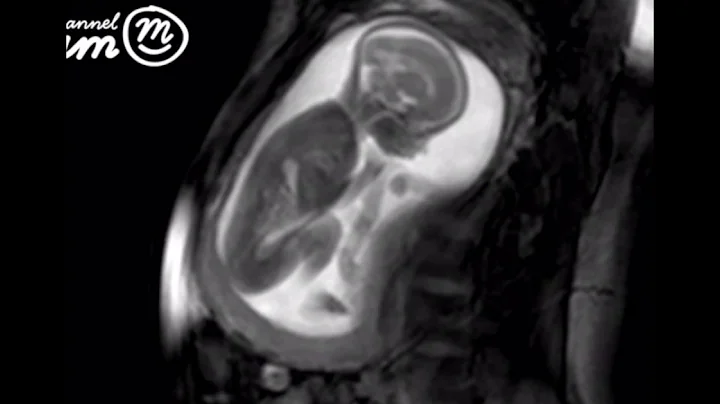

You're 21 weeks pregnant - and your baby is getting big! It's officially about the same size as the average carrot - isn't that crazy?